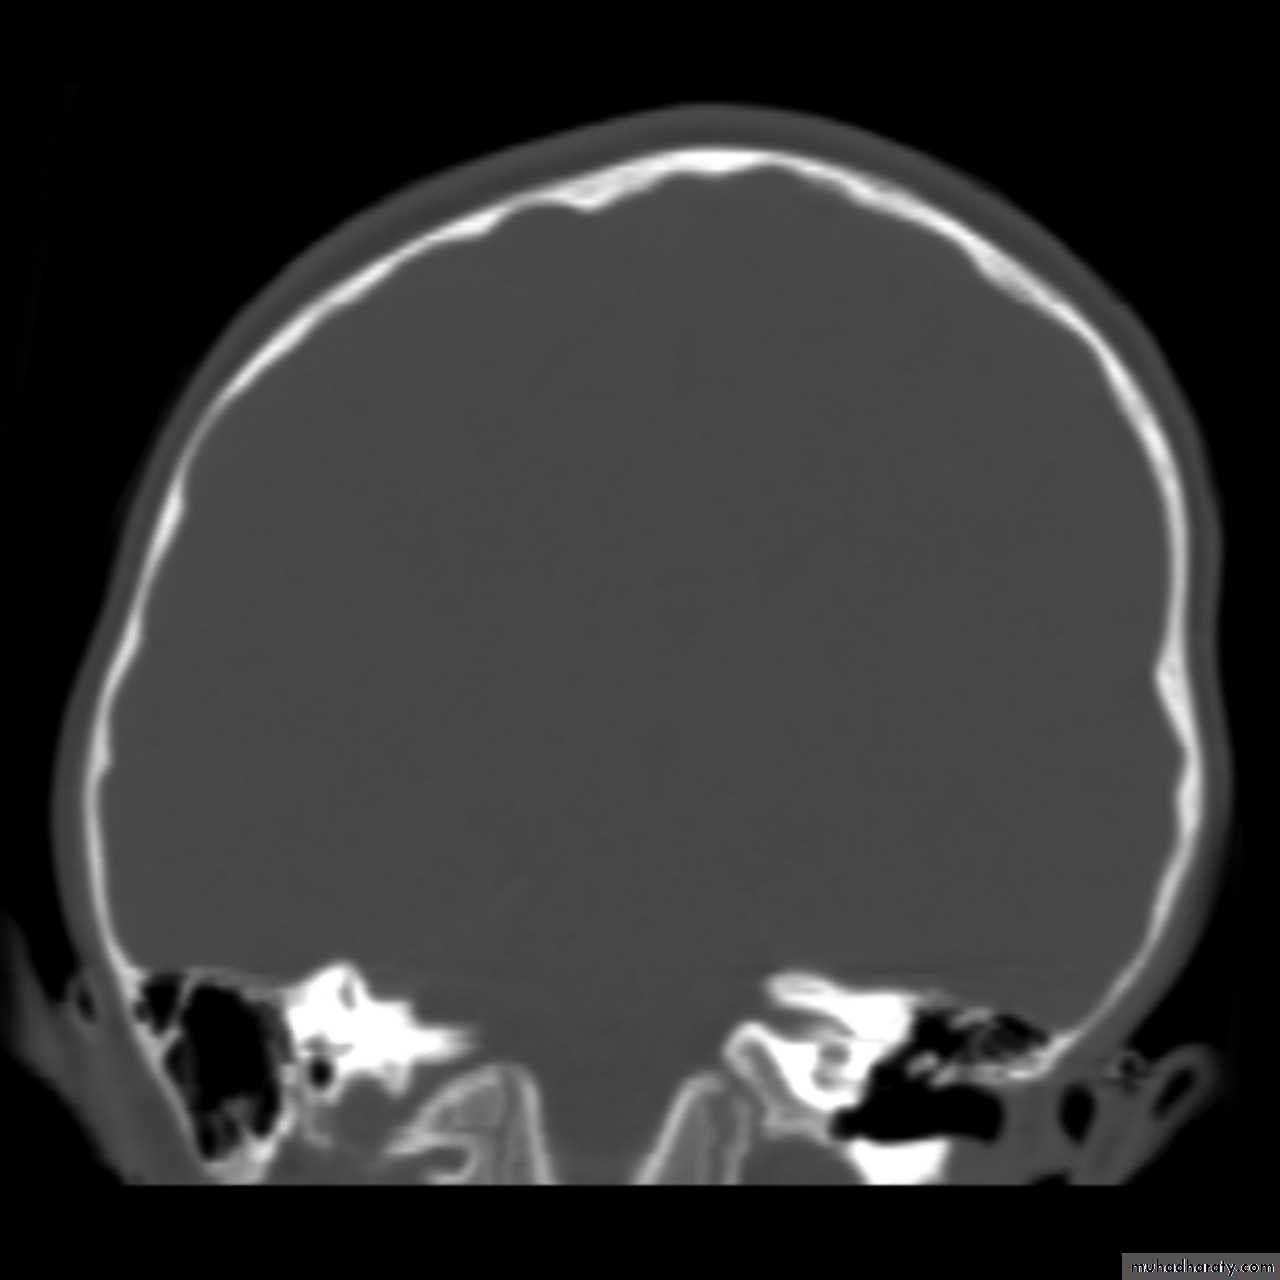

The CT and/or MRI scan will show no cause for the papilloedema and the ventricles will often be smaller than usual.

If the CT scan or MRI shows no mass or lesion a lumbar puncture is usually performed; the pressure will be raised. CSF examination is normal in benign intracranial hypertension but biochemistry and cytological investigations should be performed to exclude underlying pathology.